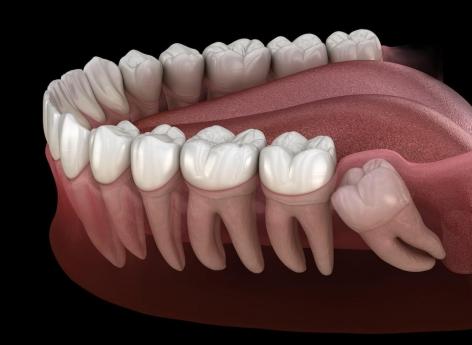

Dentition

Pour mieux apprécier le goût… faites-vous arracher vos dents de sagesse !

Les personnes qui ont enlevé leurs dents de sagesses auraient des capacités gustatives améliorées à long terme.

L’hygiène bucco-dentaire est importante pour bien apprécier le goût. Pour que celui-ci ne soit pas altéré, il est préférable d’éviter de se laver la langue. Mais dans une nouvelle étude, parue le 23 juin dans la revue Chemical Senses, des chercheurs américains de la faculté de médecine de l’université de Pennsylvanie vont plus loin et suggèrent que retirer les dents de sagesse améliorerait les capacités gustatives à long terme.

Les femmes ont toujours surpassé les hommes

Cette recherche est la première à analyser les effets de l’extraction des dents de sagesse sur le long terme. “Des études antérieures n'ont mis en évidence que des effets indésirables sur le goût après l'extraction et on pense généralement que ces effets se dissipent avec le temps, précise Richard L. Doty, auteur principal de l’étude. Cette nouvelle étude nous montre que la fonction gustative peut en fait s'améliorer légèrement entre le moment où les patients subissent une intervention chirurgicale et jusqu'à 20 ans plus tard. C'est une découverte surprenante mais fascinante qui mérite une enquête plus approfondie pour mieux comprendre pourquoi cette fonction est améliorée et ce que cela peut signifier cliniquement.”

Pour l’étude, les chercheurs ont évalué les données de 1 255 patients. Parmi eux, 891 participants se sont faits arracher leur dent de sagesse et 364 ne l’ont pas fait. Ils ont ensuite effectué plusieurs tests afin d’évaluer les fonctions gustatives des volontaires. Ils ont testé cinq concentrations différentes : saccharose, chlorure de sodium, acide citrique et caféine. Chaque solution est bue, brulée dans la bouche, puis recrachée et les participants ont dû indiquer si la solution avait un goût sucré, salé, acide ou amer.

Les fonctions gustatives améliorées entre 3% et 10%

Les résultats ont révélé que le groupe qui n’a plus ses dents de sagesse a surpassé le groupe témoin pour chacun des quatre goûts. Autre observation intéressante, les femmes ont toujours surpassé les hommes. Les chercheurs estiment que les personnes qui se sont faites extraire leurs dents de sagesse connaissent en moyenne une amélioration de 3 à 10 % de leurs fonctions gustatives. “L'étude suggère fortement que l'extraction de la troisième molaire a un effet positif à long terme, quoique subtil, sur la fonction des voies gustatives linguales de certaines personnes”, assure Dan Kim, co-auteur de l’étude.

Selon les auteurs, deux explications pourraient justifier ces résultats. La première est liée aux dommages causés par l'extraction aux nerfs qui innervent les papilles gustatives à l'avant de la bouche et qui peuvent libérer l'inhibition de ces nerfs qui alimentent les papilles gustatives à l'arrière de la bouche, augmentant ainsi la sensibilité de toute la bouche. Selon la deuxième, la chirurgie buccale qu'est l’extraction des dents de sagesse, augmente l'hypersensibilité des lésions nerveuses périphériques. Ainsi, le toucher léger répétitif, qui peut se produire pendant la mastication, accentue progressivement les réponses neuronales des tissus irrités, ce qui peut conduire à une hypersensibilité tactile progressive à long terme et pourrait stimuler la perception du goût.

“Des études supplémentaires sont nécessaires pour déterminer le ou les mécanismes derrière l'amélioration de la fonction gustative liée à l'extraction, a conclu Richard Doty. Les effets sont subtils mais peuvent donner un aperçu de la façon dont l'amélioration à long terme de la fonction neuronale peut résulter de la modification de l'environnement dans lequel les nerfs se propagent.”